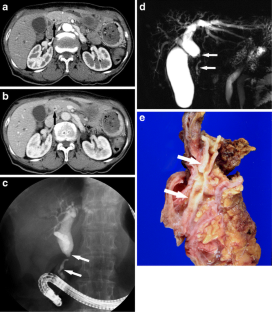

Fig. 3